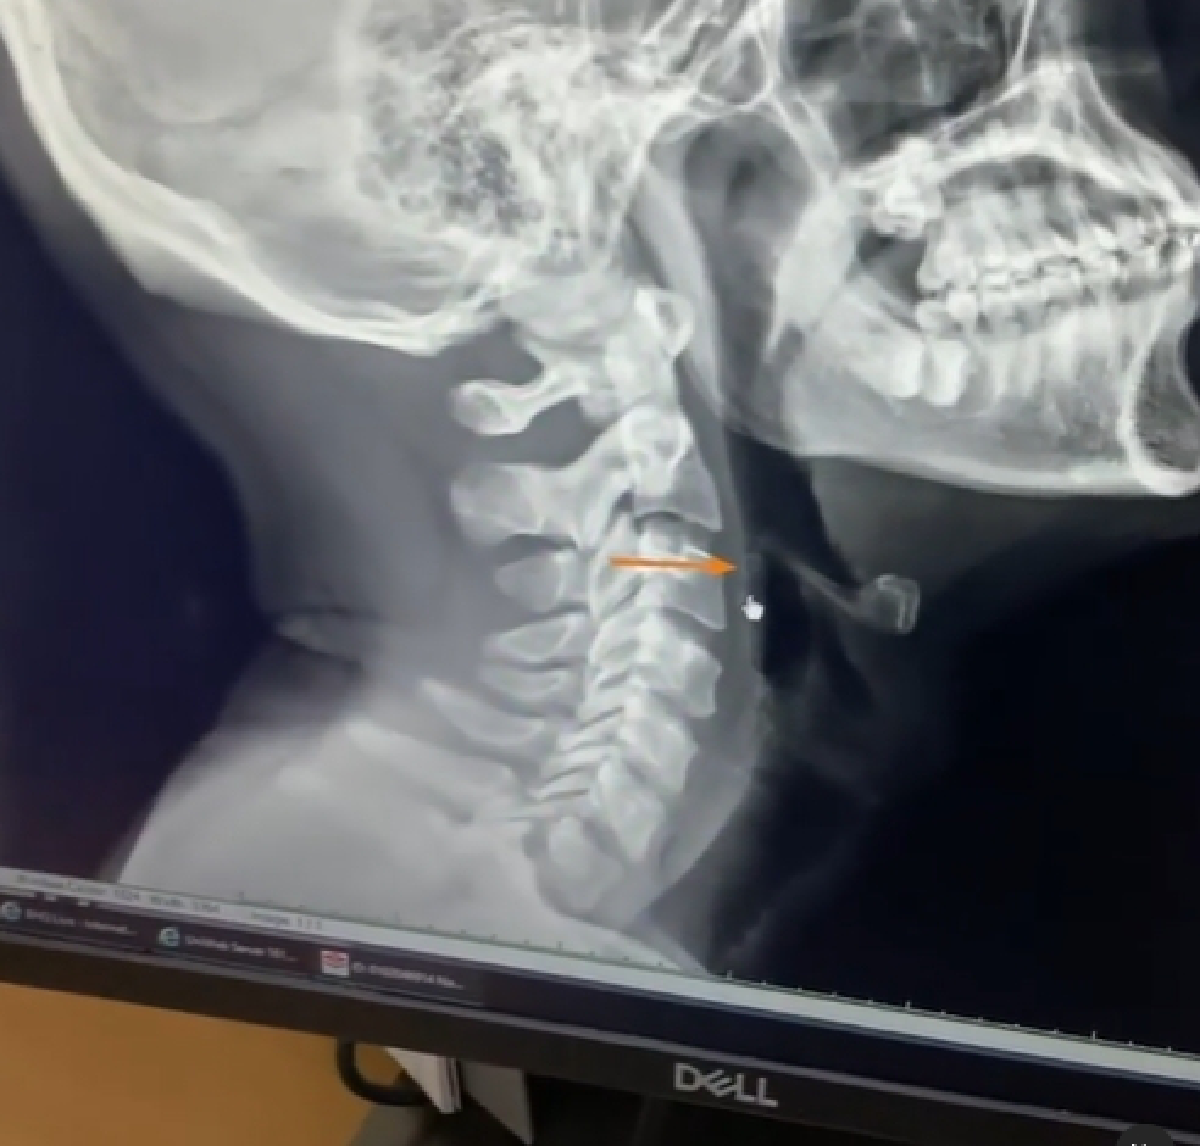

"ฉุกเฉิน! หอยบาดคอ กลืนน้ำลาย เหมือนมีหอยตำ เหตุเกิดจากซัดหอยเชลล์ที่งานเมื่อวาน ส่องกล้องก็ไม่เจอหอยหรือหอยอยู่ลึกไป"

โดยเจ้าตัวได้เผยภาพเอ็กซเรย์พร้อมกับมีแฟนคลับเข้ามาแนะนำการบรรเทาอาการครั้งนี้เพียบ ยังไงก็ขอให้หายเร็วๆนะคะ